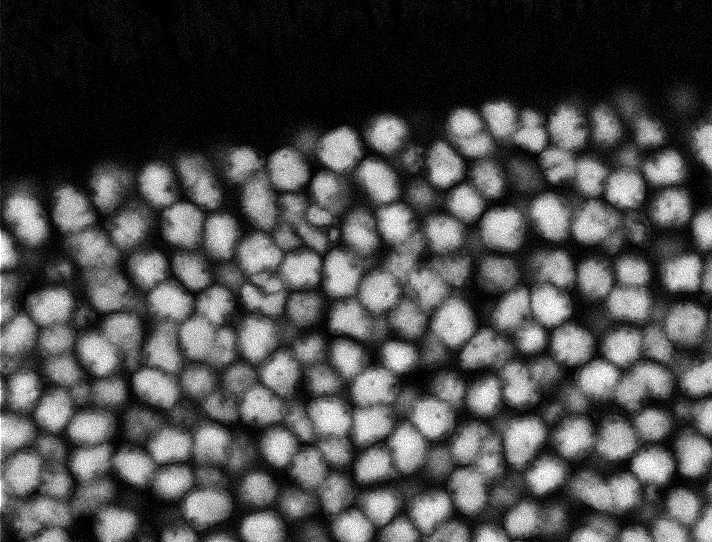

Nuclei